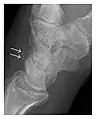

The greater tuberosity of the humerus is also an illustrative location of occult fractures. The osseous injury may follow seizures, glenohumeral dislocation, forced abduction, or direct impaction. They are commonly discovered on MRI in symptomatic patients with suspicion of rotator cuff tear. Coronal images are best suited for detection. They appear as crescentic oblique lines surrounded by a bone marrow edema pattern (Figure 5). The rotator cuff must be inspected since associated ligamentous lesions are common. In the ankle, malleoli and tarsal bones should be checked carefully for any cortical disruptions and radiolucent lines that may reveal a fracture. Awareness of the exact location of the pain will help direct the attention of the interpreter when searching for very subtle signs of fracture (Figure 6).[1]

a

b

Figure 6: Subtle anterior talar fracture in a 39-year-old man presenting with ankle pain after a fall. (a) Anteroposterior radiograph shows a subtle oblique radiolucent line through the talus (white arrows). (b) Sagittal CT reformation confirms the presence of an anterior talar fracture with cortical offset (black arrow). Avulsion fractures, which consist of a detached bone fragment resulting from a ligament or tendon pulling away from the bone, may also present with subtle radiographic signs. Tiny osseous fragments near the presumed attachment site of a ligament suggest this diagnosis. Common sites are the lateral tibial plateau (the Segond fracture), the spinal tuberosity of the tibia resulting from anterior cruciate ligament avulsion, and the ischial tuberosity.[1]